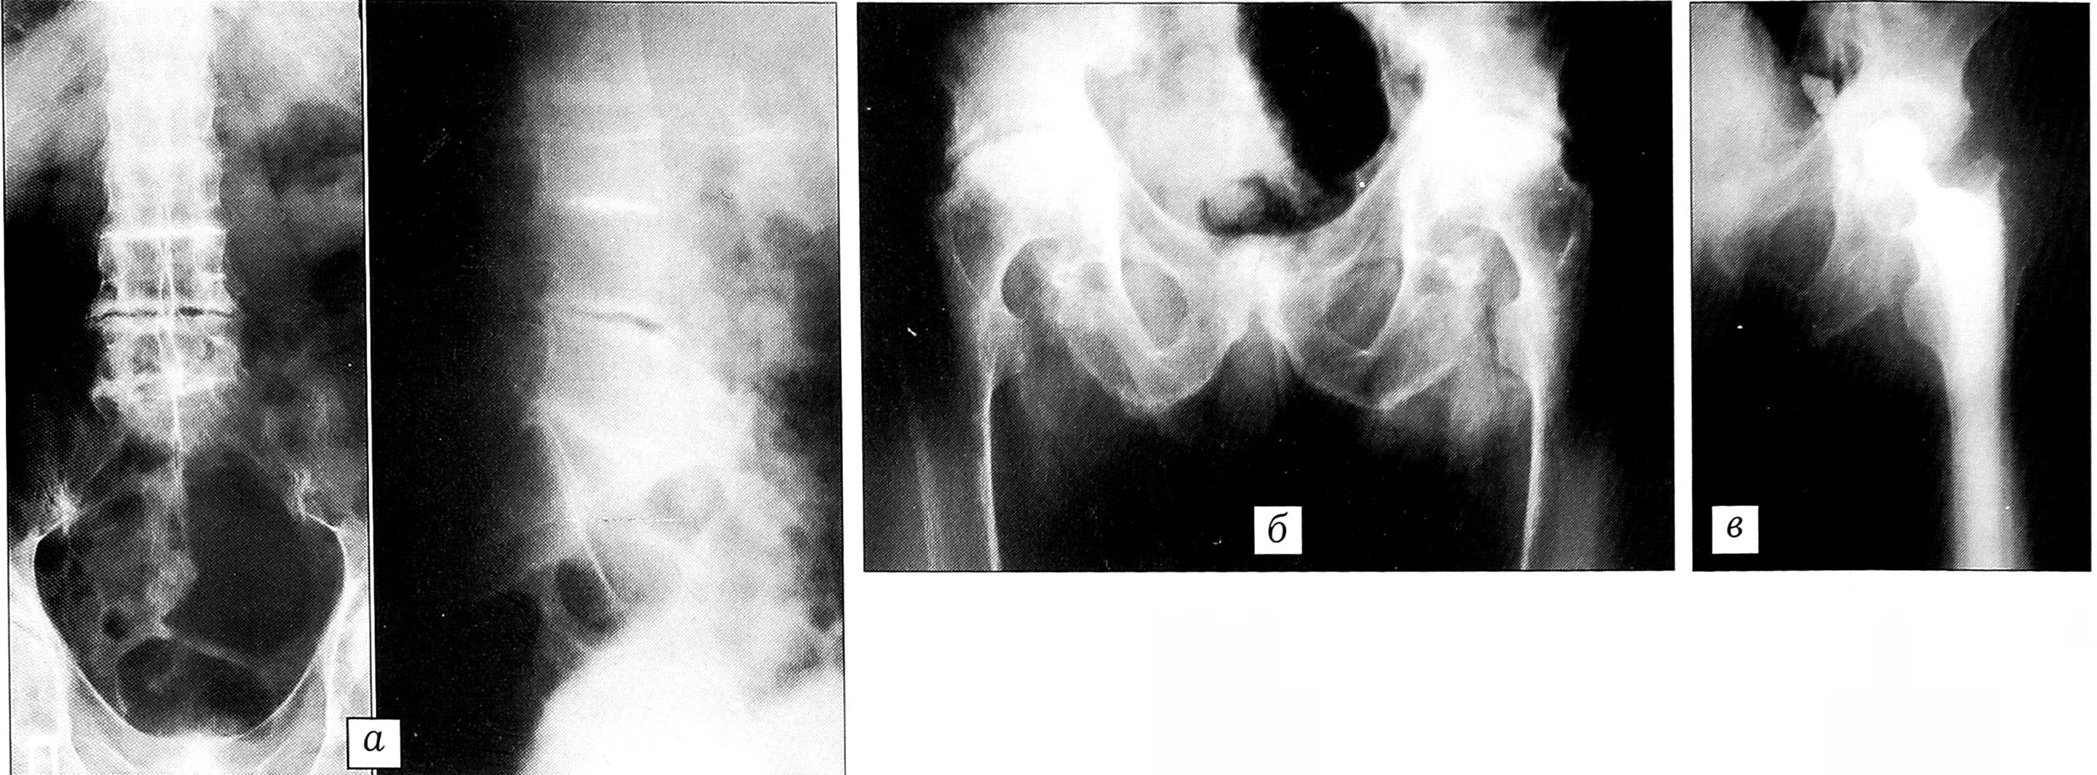

Рис. 2. Больной Н., 60 лет, диагноз: охроноз; двусторонний вторичный коксартроз; артроз обоих плечевых и коленных суставов.a — рентгенограммы позвоночника: сужение всех межпозвонковых пространств, глобальная кальцификация дисков. Остеофитоз и диффузный остеопороз. Кальцификация паравертебральных связок;б — рентгенограмма таза и тазобедренных суставов: неравномерные костные уплотнения в области лонного сочленения. Поражение тазобедренных суставов по типу деформирующего артроза;в — рентгенограмма после тотального эндопротезирования левого тазобедренного сустава протезом фирмы ЭСИ.

На рентгенограммах определяется выраженный остеопороз, высота межпозвонковых дисков резко уменьшена, вплоть до полного их отсутствия, изменения в тазобедренных суставах по типу асептического некроза головок бедренных костей (рис. 2, а, б). Лабораторные данные: анализ крови — НЬ 135 г/л, эр. 4,29*1012/л, л. 7,6109/л, СОЭ 20 мм/ч, общий белок 72,6 г/л; анализ мочи — удельный вес 1014, белок 0,033%, прозрачная, реакция кислая.

19.02.01 произведено тотальное эндопротезирование левого тазобедренного сустава протезом фирмы ЭСИ с использованием костного цемента «palacos» (рис. 2, в). Во время операции выявлены импрегнация параартикулярных тканей и хряща головки бедренной кости темнокоричневым пигментом, разрушение хрящевого покрытия, выраженный остеопороз вертлужной впадины и проксимального отдела бедренной кости.